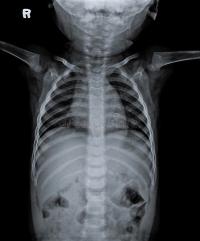

Pioneers in pediatric radiology

Radiologists at Babies Hospital establish the first pediatric radiology service.

Advances in Radiology

Dr. John Caffey publishes the comprehensive text, Pediatric X-Ray Diagnosis, which establishes the intellectual basis of pediatric radiology. Dr. Caffey also publishes a description of infantile cortical hyperostosis, now known as “Caffey disease,” and shortly after that the first description of “shaken baby syndrome.”